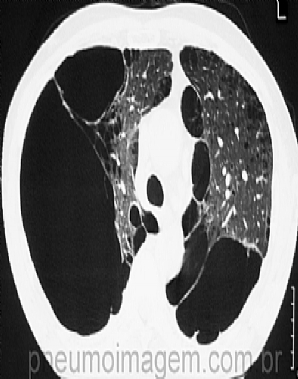

Veja imagens sobre DPOC no PneumoImagem, clicando aqui.